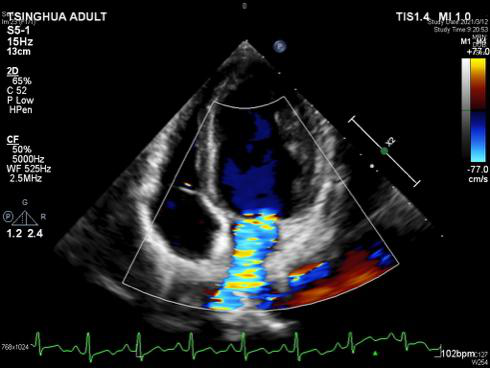

同样的故事,还发生在来自内蒙的老布仁特古斯身上。今年57岁的老布仁特古斯,因频繁出现活动后气喘,胸闷,被当地医院确诊为二尖瓣腱索断裂,出现大量反流,需尽快进行手术。为寻求更好的医治,一家人不远千里来到崔晓征的门诊。医生的直觉告诉他,情况紧急,老布仁特古斯不能再拖下去了,他一面安抚患者和家属,一面联系ICU为患者提供床位。住院仅两天后,崔晓征与李温斌为老布仁特古斯行二尖瓣成形手术,避免了瓣膜置换术后因长期抗凝导致出血等并发症。术后心脏超声显示,二尖瓣返流由术前的重度变成了微量,手术成功。